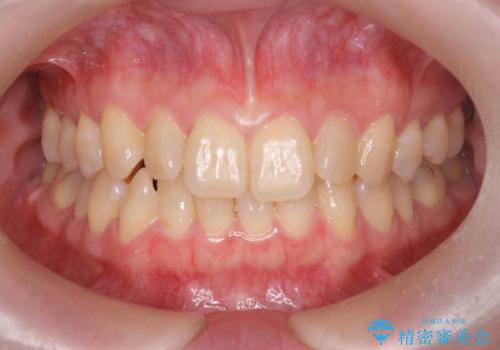

【ワイヤー矯正】八重歯 歯のでこぼこを治したい!